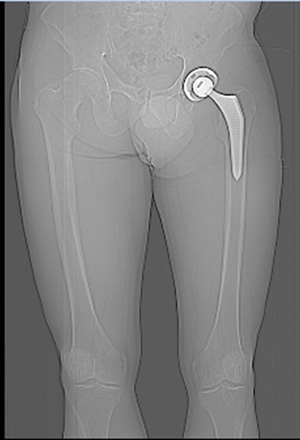

Abbildung Hüft / Teil Rücken / Teil Beine von hinten aufgenommen

1.5

1.6

Hüft mit Strichen Pfeilen Kreise sichtbar gemacht

Oberkörper weicht trotz Hüftgelenk Ersatz blau eingesetzte Striche aus.

Anhand der Gesässfalten wird auch der Beckentiefstand ersichtlich.

Über die Grüne Linie sieht man wie die rechte Seite geknickt wird.

Auf der linken Seite wird die Überdehnungsspannung sichtbar.